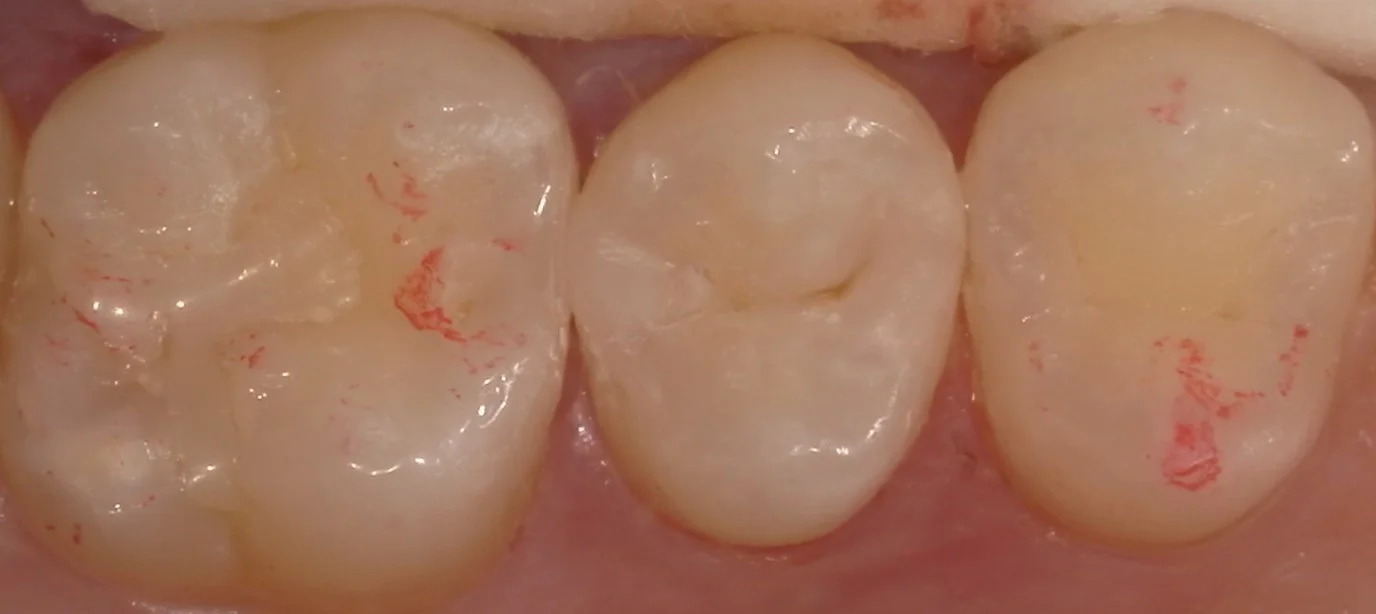

そして詰め終わったのがこの状態です。

違和感なく仕上げられたかと思います。

患者さん自身、喜んでいただけました。

また余談ですが、この方は日ごろの定期健診を行う医院を新しく見つけ、かかった所、そちらの歯科医師からも綺麗だと言って頂けたようです。

しっかりとケアしてなるべく長く使っていただければ幸いです。